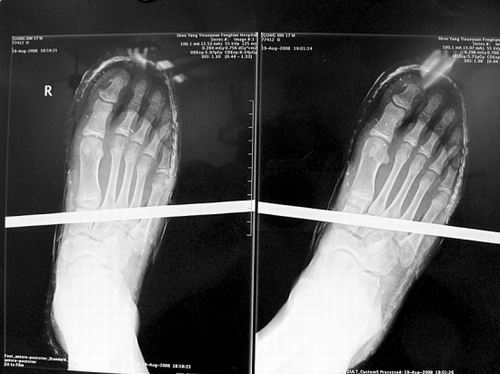

X光片顯示無(wú)大礙

事發(fā)時(shí)男孩穿著一雙布鞋,骨外二科陳賓醫(yī)生操起剪刀,將布鞋一塊塊剪掉。經(jīng)X光透視,醫(yī)生驚奇地發(fā)現(xiàn):男孩雖然被鋼筋穿透了右腳,但骨頭、大的血管和神經(jīng)都沒(méi)受任何傷害!

20日,記者從X光片子上看到,鋼筋避開(kāi)了男孩腳掌骨頭密集的部位,而是從腳弓處穿過(guò),這個(gè)部位基本上以軟組織為主。“真沒(méi)想到,太神奇了!”幾名醫(yī)生連聲感嘆,術(shù)中,他們分工合作,小心翼翼地將鋼筋取出,并做了引流、清創(chuàng)、包扎。